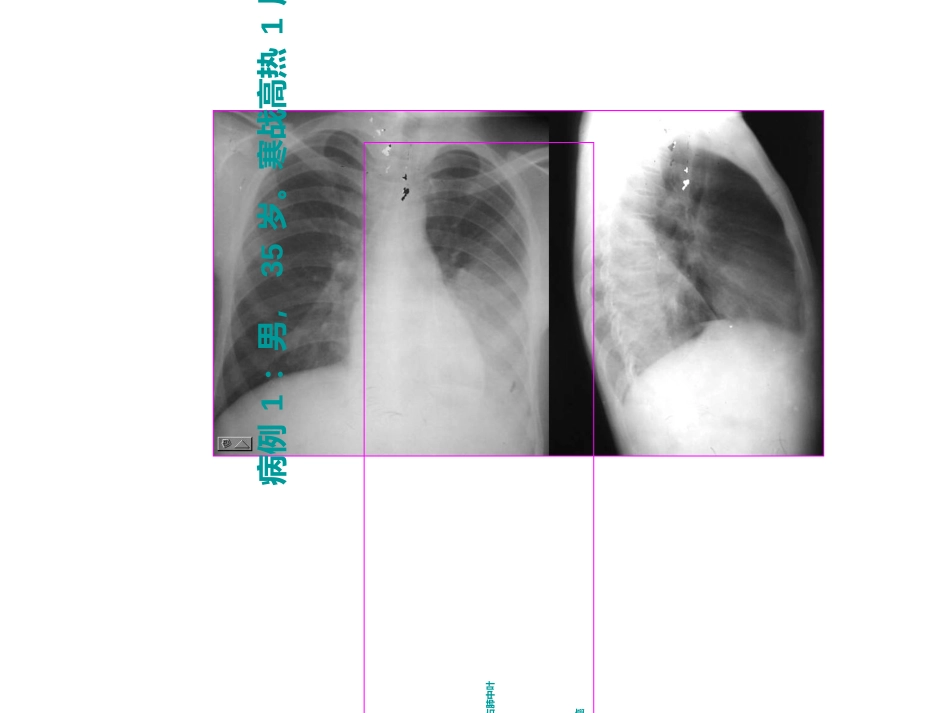

2016医师实践技能考试影像部分桂林医学院附属医院放射科杨新官副教授2016年6月病例1:男,35岁。寒战高热1周。•请选择:.1.1病变部位(病变部位(0.50.5分)分)::a.左肺下叶;b.左肺舍叶;c.右肺下叶;d.右肺中叶.2.2诊断(诊断(0.50.5分)分)::a.肺炎;b.肺不张;c.肺结核;d.中央型肺癌病例2:男,56岁。吞咽梗阻3月。•请选择:.1.1诊断(诊断(11分)分)::a.a.溃疡型食管癌溃疡型食管癌b.b.髓质型食管癌髓质型食管癌c.c.肿块型食管癌肿块型食管癌d.d.缩窄型食管癌缩窄型食管癌病例3:男16岁,头部外伤2小时。•1.请给出诊断(1分):•a.急性硬膜外血肿;b急性硬膜下血肿;c.c.慢性硬膜外血肿;慢性硬膜外血肿;d.d.慢性硬膜下血肿慢性硬膜下血肿。。病例4:患者,40岁,咳嗽、咳痰、盗汗5月。1.请选择正确的诊断(0.6分):a.右上肺大叶性肺炎b.右上肺脓肿c.右上肺继发性结核d.过敏性肺炎2.该患者是(0.4分):a.男性b.女性c.不能确定病例5:男,发现大腿下份包括1年。1.请选择正确的诊断(0.6分):a.骨肉瘤b.软骨肉瘤c.骨软骨瘤d.骨瘤2.指出病变部位(0.4分):a.骨端b.干骺端c.骨干d.骨骺病例6:男,32岁,腰痛伴血尿8月。1.请给出诊断(1.0分):a.双肾多发结石b.左输尿管上段结石c.右肾自截伴左肾输尿管多发结石d.双肾输尿管结核病例7:男,55岁。咳嗽胸痛1月。1.请根据上述影像表现,给出正确的诊断(0.6分):a.多发性肺含液囊肿b.多发性肺脓肿c.多发性转移瘤d.多发性结核瘤2.这个CT图像应用的窗技术(0.4分)是:a.肺窗b.纵隔窗c.骨窗d.脑窗病例8:男,56岁,咳嗽、咳血丝痰1月。1.请选择正确的诊断(1分):a.右肺上叶肺不张b右肺上叶肺炎c右肺干酪性肺炎d右肺上沟瘤病例9:男,31岁,突发头痛呕吐3小时。请给出正确诊断(1分):a.结核性脑膜炎b.化脓性脑膜炎c.蛛网膜下腔出血d.硬膜下出病例10:男,20岁,外伤后1天1.请给出正确诊断(1分):a.肱骨髁上骨折b.肱骨髁下骨折c.桡骨骨折d.尺骨骨折病例11:腰痛伴肉眼血尿1天请给出正确诊断(1分)a.右肾阳性结石b.右肾阴性结石c.右输尿管阳性结石d.右输尿管阴性结石病例12:体检发现肝脏肿块。1.请给出正确诊断(0.6分):a.巨块型肝癌b.肝血管瘤c.肝腺瘤d.肝转移瘤2.该病变(0.4分):a.位于肝右叶b.位于肝左叶c.病变延迟期呈高密度d.病变延迟期呈低密度病例13:咳嗽、盗汗、咯血2年1、请给出正确诊断(1分):a.左上肺不张b.左上肺大叶性肺炎c.左上肺干酪性肺炎d.左上肺慢性纤维空洞性结核病例14:手外伤1小时。1.请给出正确诊断(1分):a.第五掌骨远侧干骺端骨折b.第一掌骨远侧干骺端骨折c.第五指骨骨折d.第一指骨骨折病例15:老年女性,跌伤1天。1.诊断(1分):a.股骨颈骨折b.粗隆间骨折c.没有骨折d.先天发育异常病例16:女,50岁,上腹痛8月。1、请给出正确诊断(1分):a.胆囊结石b.胆总管结石c.肝内胆管结石d.胃结石病例17:胸痛5天。1.请给出正确诊断(1分):a.右侧液气胸、右肺压缩b.左侧液气胸、左肺压缩c.右肺炎伴胸腔积液d.左肺炎伴胸腔积液病例18:肉眼血尿2月。1.该两幅图像是否同一患者(0.4分):a.是b.不是c.不能确定2.病变性质(0.6分):a.膀胱结石b.淋巴结钙化c.宫内节育器d.盆腔畸胎瘤病例19:男,65岁,突发头痛3小时。1、请给出正确诊断(1分):a.右侧基底节脑内血肿并脑室内积血b.左侧基底节脑内血肿并脑室内积血c.右侧颞叶脑梗死d.左侧颞叶脑梗塞病例20:男,30岁,咳嗽、发热、盗汗20余天。1.请给出可能性最大的诊断(1分):a.急性粟栗性肺结核b.肺泡蛋白沉着症c.弥漫性肺泡癌d.双肺转移瘤病例21:男,13岁,咳嗽、寒战、发热7天。1.请给出可能性最大的诊断(1分):a.右肺中叶大叶性肺炎;b.右肺下叶大叶性肺炎;c.右肺中叶肺不张;d.右肺中叶肺结核。病例22:外伤5天。1.请给出正确诊断(1分):a.L4压缩性骨折b.L5压缩性骨折c.L4结核d.L5结核9-1病例23:男54岁,消瘦、解黑大便3月。1.病变性质(0.6分)a.b.c.d.2.病变部位(0.4分)a.b.c.d.病例23:咳嗽、寒战、发热8天。1、请给出正确诊断(1分):a.b.c.d.病例24:头部外伤3小时。•1、病变部位(0.4分):a、硬膜外;b...